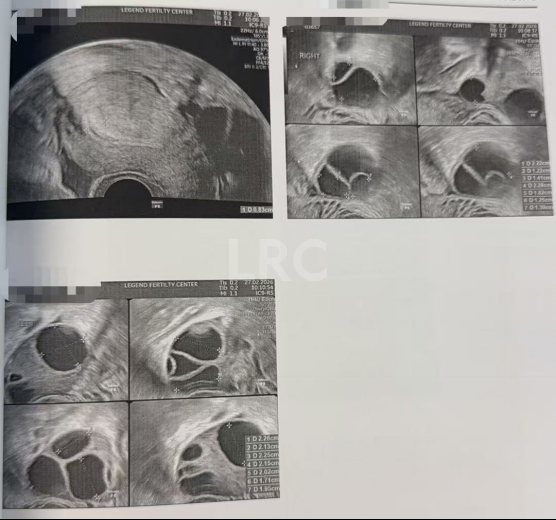

月经第二天 促排第一天

阴超检查:基础卵泡 15 颗

- 右侧卵泡 6 颗 (5-6mm)

- 左侧卵泡 9 颗 (6-7mm)

促排第五天

阴超检查:

- 右侧卵泡 6 颗 (12,10,10,9,8,6mm)

- 左侧卵泡 8 颗 (12,12,11,10,10,10,9,9mm)

激素水平检查:

- 促黄体生成素 3.52 miu/ml

子宫内膜厚度:5.00 mm

促排第八天

- 右侧卵泡 5 颗 (21,19,15,14,13mm)

- 左侧卵泡 8 颗 (20,18,16,15,14,13,12,11,11mm)

子宫内膜厚度:9.00 mm

促排第九天

- 右侧卵泡 6 颗 (22,22,17,16,12,12mm)

- 左侧卵泡 8 颗 (22,21,20,20,18,18,17,14,14mm)